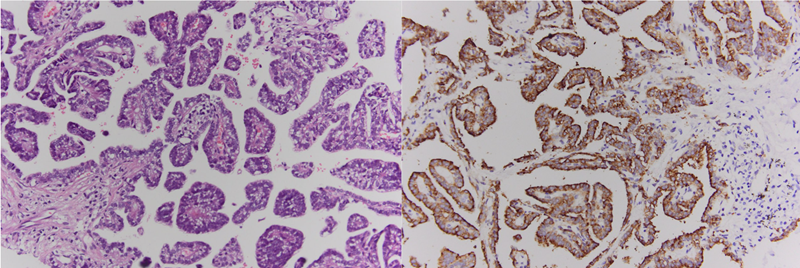

Kết quả mô bệnh học và hóa mô miễn dịch cho thấy đây là ung thư biểu mô tuyến nhú của phổi, các tế bào u dương tính TTF-1, Napsin A, CK7. Đây là phân nhóm hiếm của ung thư phổi không tế bào nhỏ, đặc trưng bởi cấu trúc nhú, khả năng xâm lấn và di căn cao, tiên lượng phụ thuộc lớn vào phát hiện sớm.

Kết quả mô bệnh học và hóa mô miễn dịch cho thấy đây là ung thư biểu mô tuyến nhú của phổi